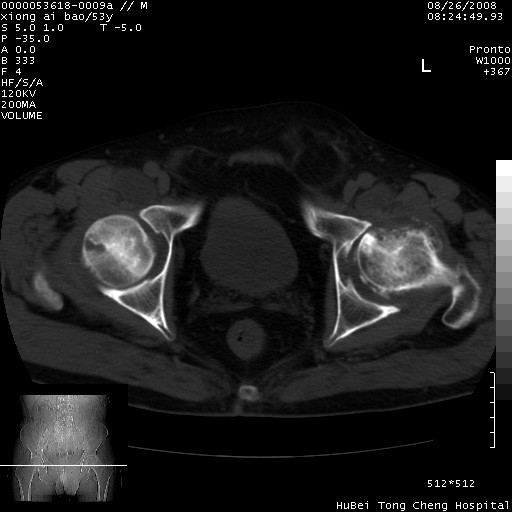

标题: CT15583:M,53Y。请老师指教分析骨盆及其他病变。 [打印本页]

标题: CT15583:M,53Y。请老师指教分析骨盆及其他病变。

股骨头坏死/腹股沟疝。

双侧股骨头无菌坏死,左侧腹股沟斜疝。

非常典型病例,双侧股骨头坏死伴双髋关节周围软组织肿胀,左腹股沟疝。

双侧股骨头坏死伴双髋关节周围软组织肿胀,左腹股沟疝。

双侧骨股头无菌性坏死,左侧腹股沟疝

双侧髋关节肿胀明显,感觉还不能排除结核。

考虑双侧髋关节结核,左侧腹股沟疝